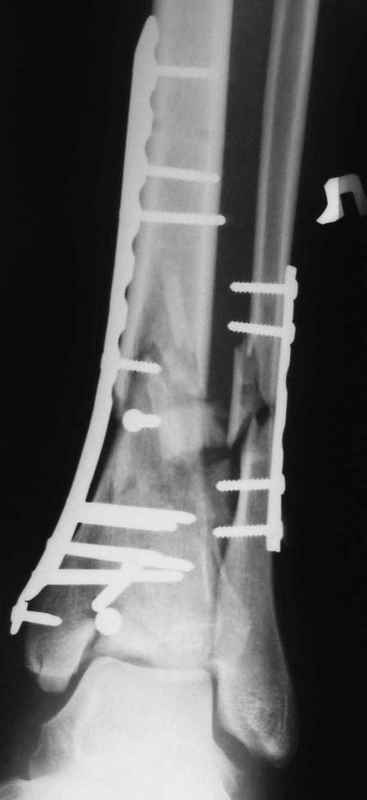

Да кстати нашёл похожий случай для пилона.Малоинвазивная дистальная пластина LCP у вас я думаю есть опыт их использования ну очень хорошая. Очень стабильно получается.